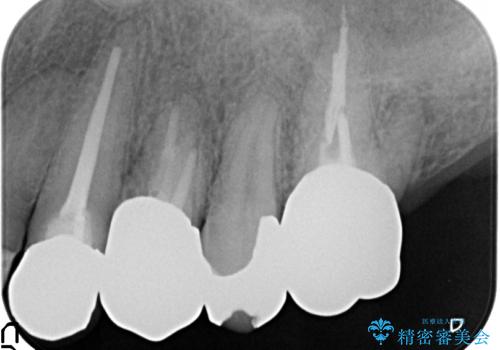

PGA(ゴールド)クラウン 脱離した銀歯の治療

再根管治療後、PGA(ゴールド)クラウンによる補綴を行いました。

- PGA(ゴールド)クラウン…¥80,000、仮歯…¥10,000、ファイバーコア…¥20,000費用は治療当時の料金となります

ゴールドは化学的な安定性が高いため変色や腐食がほとんどなく、アレルギーなども起こりにくい人体に優しい素材です。

また硬さも天然歯に近いため周囲の歯への影響も少なく、さらに適合もよいため虫歯の再発も少ない、とても補綴に適した材料です。